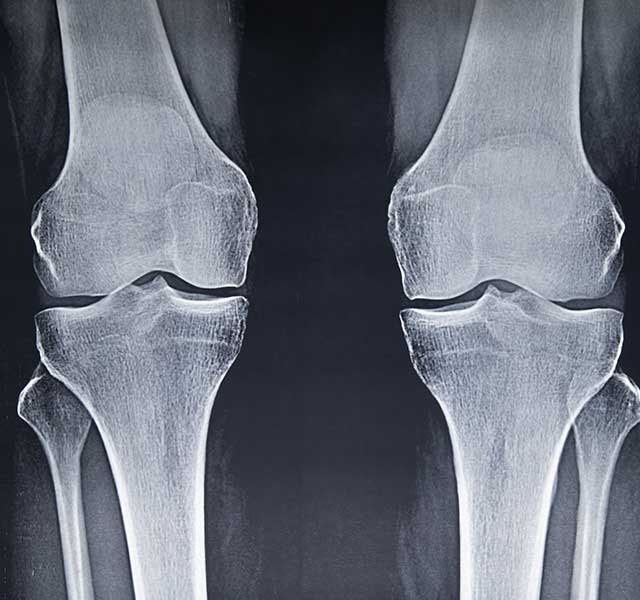

Osteoarthritis – a degenerative joint disease – can be challenging to live with. It causes pain and stiffness, making it difficult to go about your daily life. Virtually no one is immune to it as they get older, since it’s caused by cartilage wearing down over the years, says Ramsey Shehab, M.D., a sports medicine physician at Henry Ford Health.